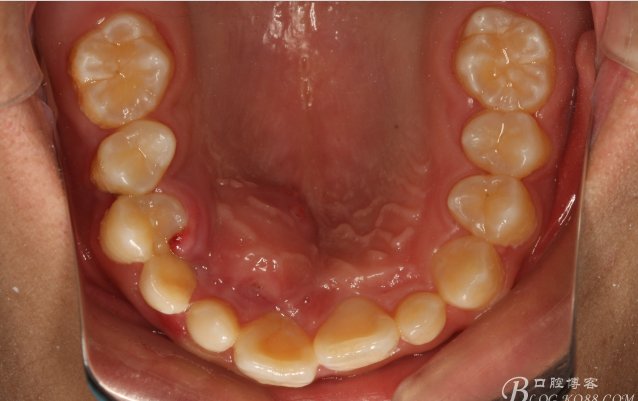

圖4.上腭部影像:腭側(cè)粘膜圓形隆起